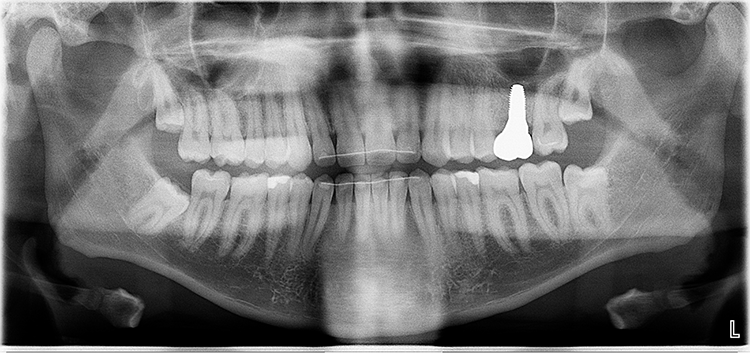

Der 26-jährige Patient stellte sich mit dem Wunsch einer Neuversorgung seiner Kompositrestauration an Zahn 22 vor (Abb. 6). Sie sei bereits mehrfach repariert worden, und aus diesem Grund wünsche er jetzt eine Veneerversorgung. Der Patient wurde dahingehend aufgeklärt, dass zwar eine Veneerversorgung durchaus im Indikationsspektrum für derartige Lückenschlussversorgungen liege [3,4,6,8,21,23,31,35,38], dies aber eindeutig als Überversorgung zu werten wäre, da identische ästhetische Versorgungsergebnisse durchaus mit direkten Kompositanbauten erzielt werden könnten. Prof. Dr. Ernst

Die zu ersetzende Vorrestauration am Zahn 22 zeigte eine Fraktur des Aufbaus im inzisalen Bereich sowie einen insuffizienten Übergang approximal-zervikal: Hier war eine positive Stufe sicht- und tastbar. Oft ergeben sich derartige Stufen aus einer insuffizienten Formgebung der Restauration, die kein aus der Tiefe des Sulkus herausreichendes Emergenzprofil erlaubt (Abb. 6). Nach vollständiger Entfernung der Vorrestauration und der darunter überraschend zu Tage getretenen, nicht unerheblichen Sekundärkaries erfolgte die Verschalung des Defektes zur Formgebung mit einer vertikal inserierten und mit einem niedrigviskösen lichthärtenden Provisoriummaterial (Clip Flow, VOCO, Cuxhaven) fixierten Teilmatrize (Composi-Tight 4,6 mm Prämolaren Matrizenband, B-Serie, Garrison, Abb. 7). Prof. Dr. Ernst